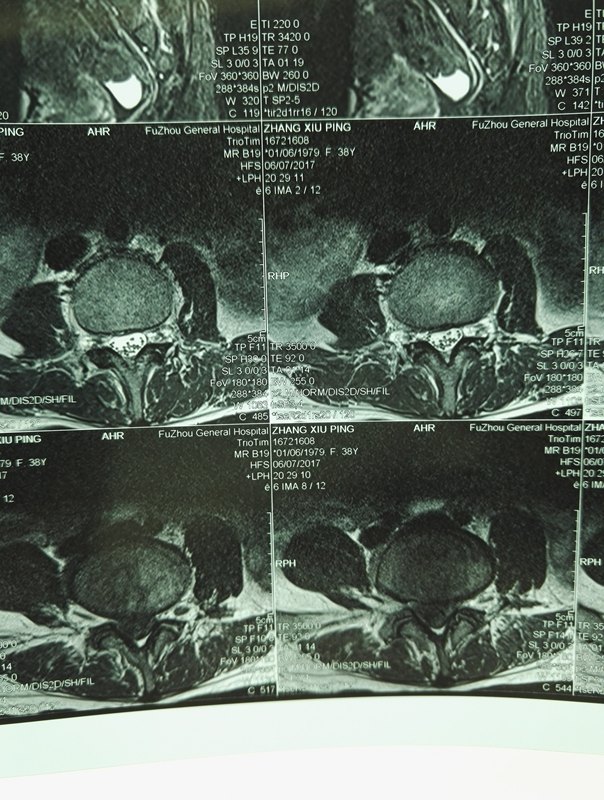

微創(chuàng)取出巨大髓核巨大椎間盤突出,疼痛無法平臥,夜里無法入睡。由于微創(chuàng)的工作套管只有7.5MM。該病人髓核巨大,長(zhǎng)50MM,寬15MM??ㄓ诠ぷ魈坠苣┒?,最后只能采用非常規(guī)方法,連同工作套管一起拔出。 患者癥狀立刻緩解。

椎間盤的纖維環(huán)破裂,內(nèi)部的髓核經(jīng)破口外突。從人類直立行走,椎間盤受縱向及屈曲各種力量,隨年齡增加,其退變老化不可避免。在此基礎(chǔ)上,不斷的反復(fù)外力損害,特別是某次特別大的彎腰、負(fù)重,會(huì)使纖維環(huán)出現(xiàn)較大破口,髓核隨之突出?,F(xiàn)實(shí)中,髓核可以向前后左右突出,只有當(dāng)壓迫神經(jīng)時(shí),才需要處理。